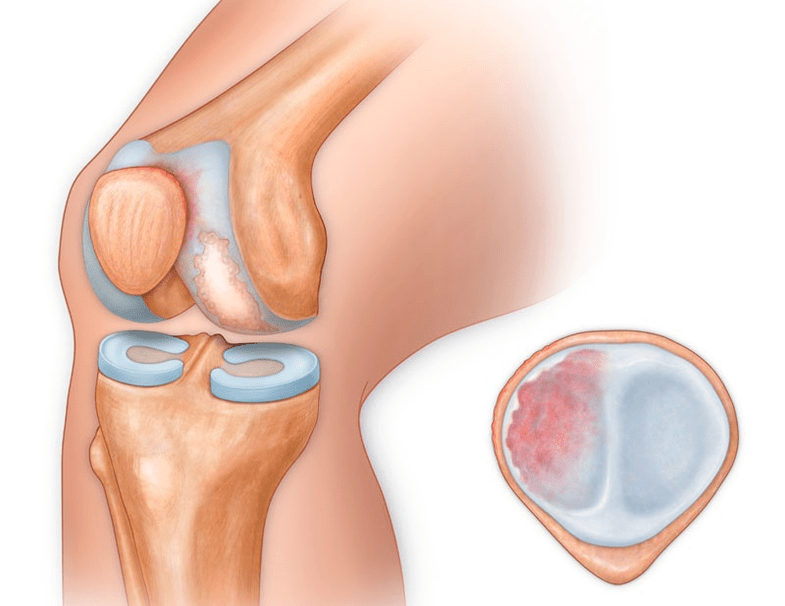

Neben dem inneren oder äußeren Teil des Knies kann Arthrose auch die Oberflächen zwischen der Kniescheibe und der interkondylären Rinne des Femurs betreffen. Diese Option heißt patellofemorale Arthrose.

Die Ursache liegt meist in einer Subluxation, Fraktur oder Lateralisierung der Patella.